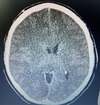

20 anos, puérpera com cefaleia e convulsões. Qual diagnóstico?

PRESS Encefalopatia posterior reversível